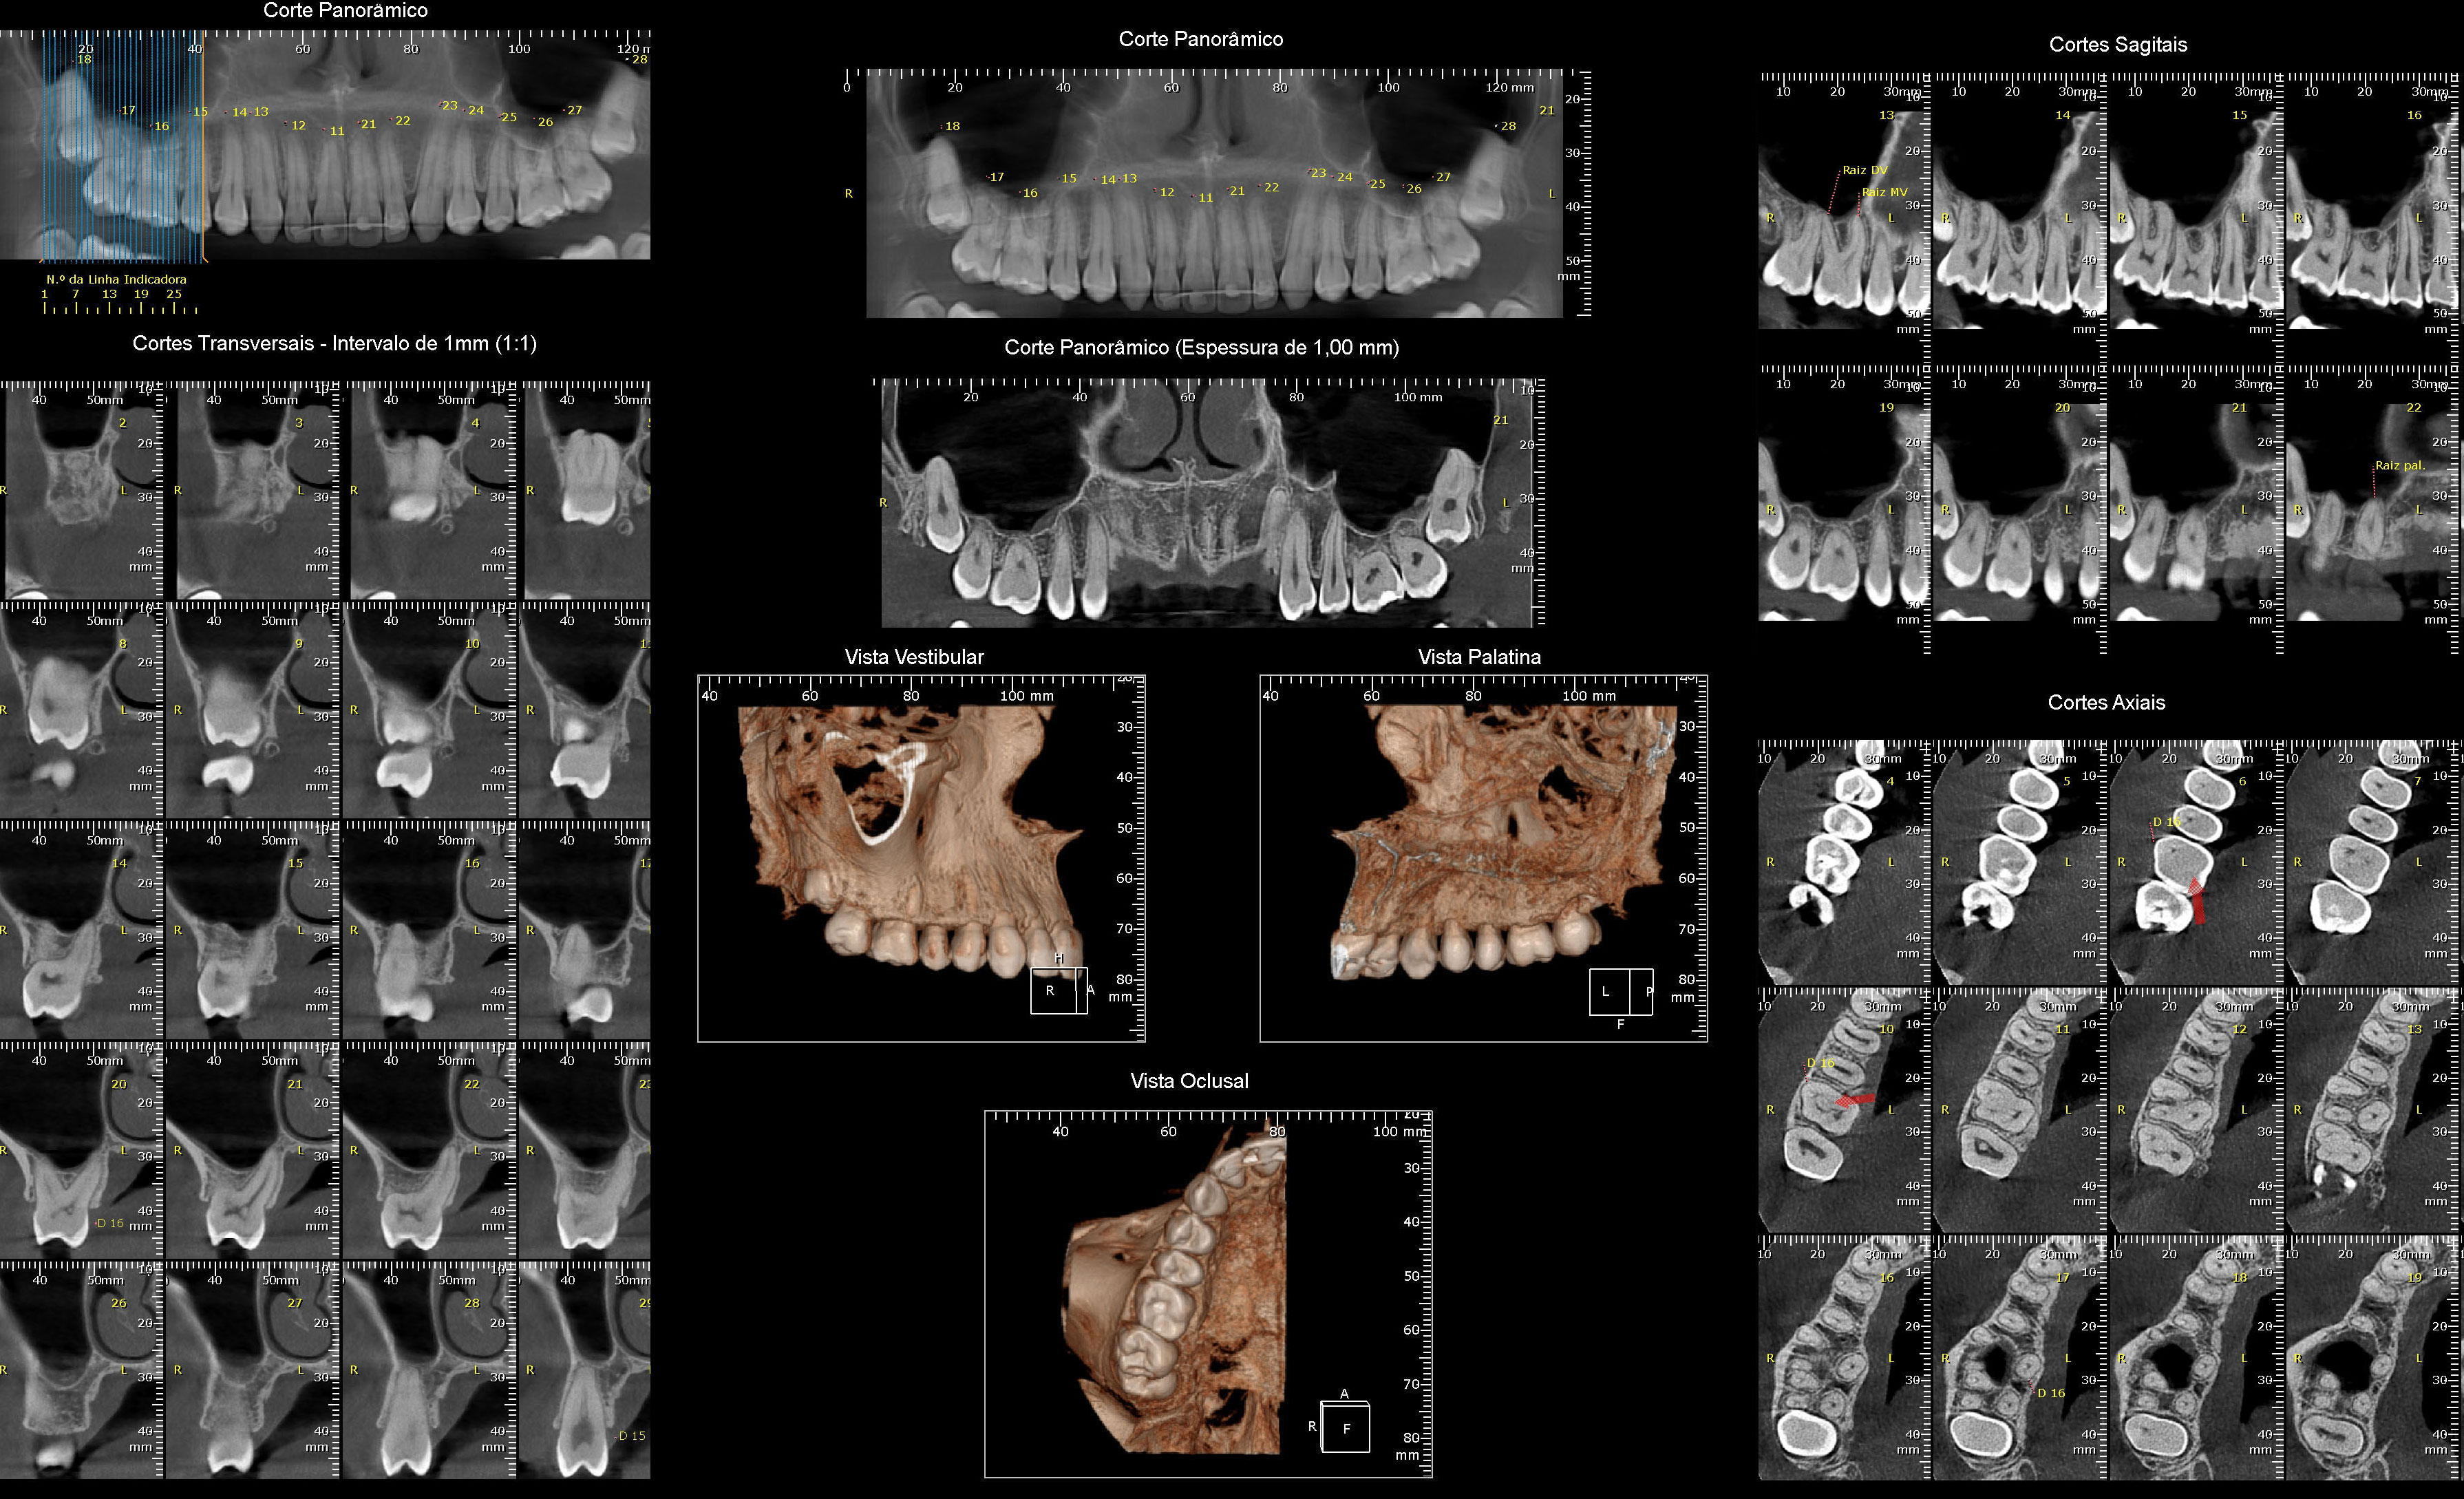

Tomografia Computadorizada

- Exame Tridimensional dos Maxilares

- Tomógrafo de Altíssima Resolução